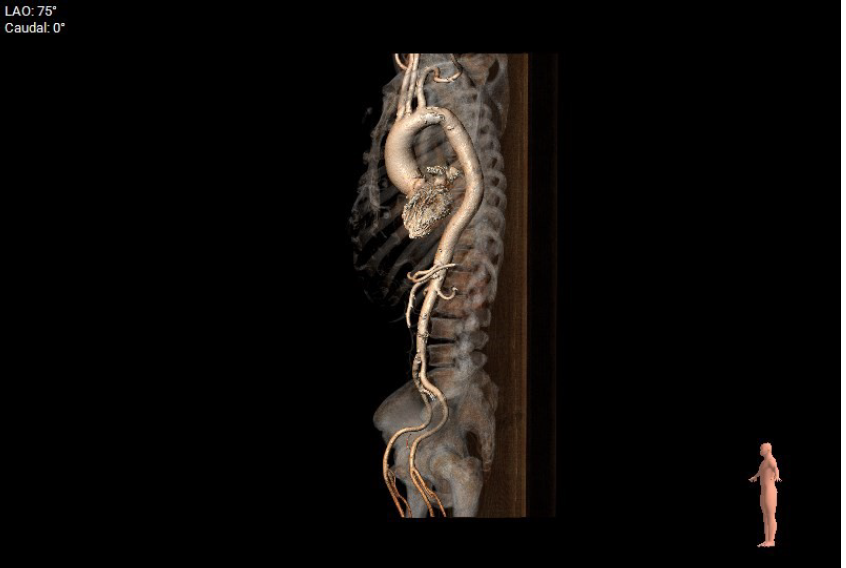

主动脉瓣结构分析:

type 1型主动脉瓣,左右融合,瓣叶增厚,重度钙化,钙化分布于三窦瓣叶。

瓣环周长87.4mm,均径27.8mm;LVOT周长90.6mm,均径28.8mm。

瓣上4/6/8mm预估可推开周长为81.1、79.2、77.5mm。

建议20mm球囊预扩,TAV27瓣膜,备24瓣膜。

极重度钙化,存在瓣周漏可能。

术中DSA影像